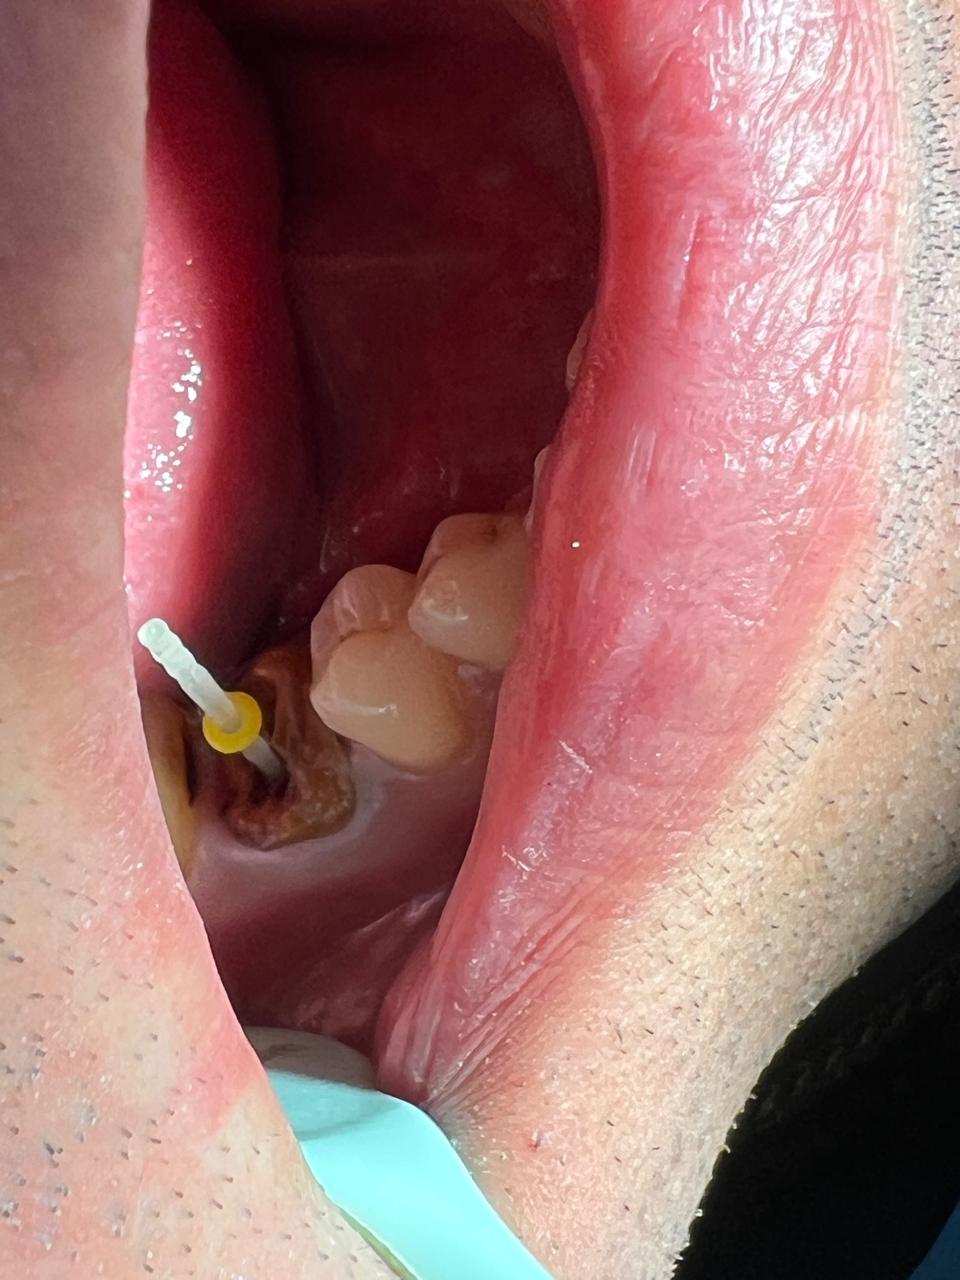

Clinical Findings

Upon examination, an intraoral sinus tract was observed adjacent to a previously root canal-treated tooth. The tract was non-tender but discharged pus on slight pressure. The crown appeared intact externally.